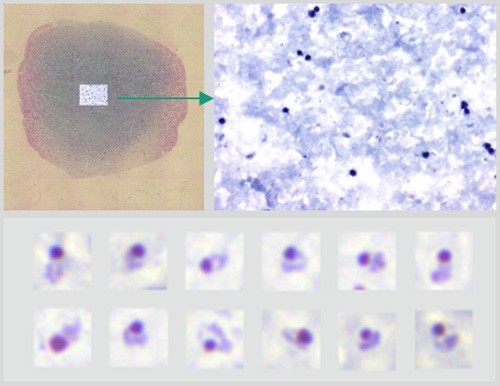

Раздел: Фотопутеводитель